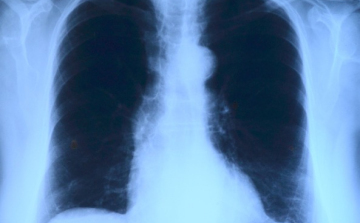

Elvégezték az országban az első tüdőverőér-tágítást

Az országban elsőként a Debreceni Egyetem Klinikai Központjában végeztek tüdőverőér-tágítást - közölte a felsőoktatási intézmény sajtóirodája kedden az MTI-vel.

Már a 26. tüdőátültetést végezték el Magyarországon

A 26. tüdőátültetést végezték el Magyarországon a közelmúltban - közölte az Országos Onkológiai Intézet és a Semmelweis Egyetem hétfőn az MTI-vel.